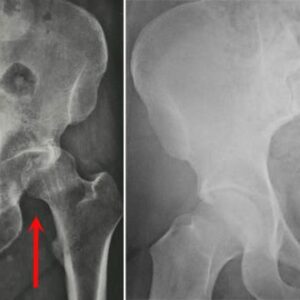

Hip Patient informationA hip fracture refers to a break in the upper segment of the femur, commonly known as the thighbone. These fractures are most frequently seen in older adults with weakened bones due to osteoporosis. However, in younger individuals, hip fractures typically result from high-impact incidents, such as falling from a